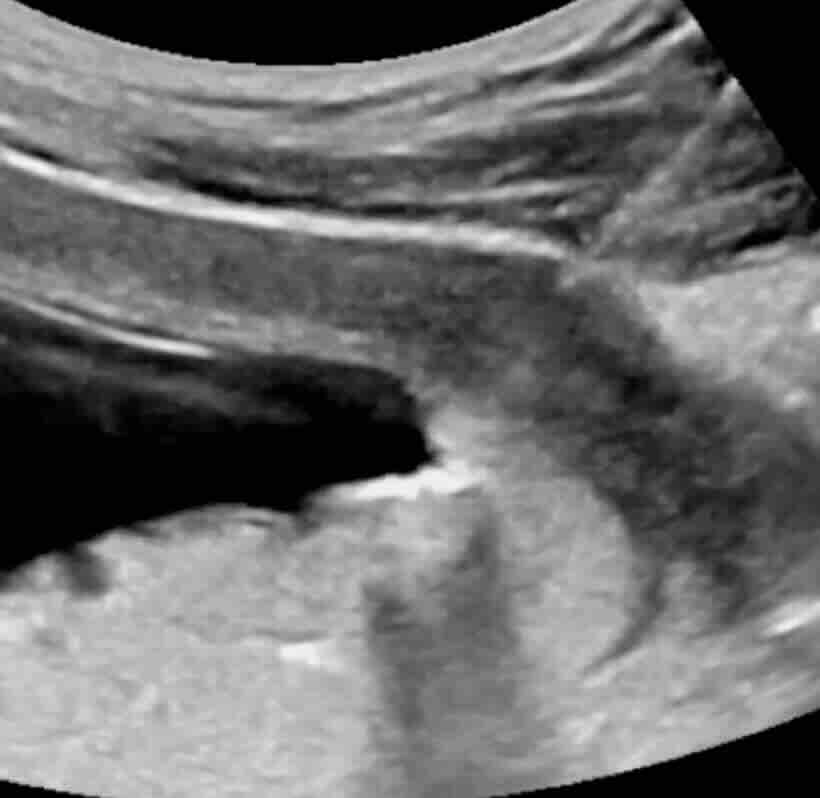

Rahim filmi, rahim iç boşluğunu ve tüplerin açıklığını değerlendirmek için yapılan özel bir röntgen görüntüleme yöntemidir.

Bu işlem sırasında rahim içine kontrast madde verilir ve röntgen altında görüntü alınır. Eğer tüpler açıksa kontrast tüplerden karın içine yayılır. Eğer tıkanıklık varsa kontrast ilerlemez ve bu durum net şekilde görülür.